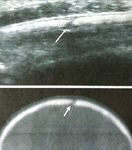

e acido palmitico, Levovist, Schering, Berlino,                   Figura 1. Vescica distesa, con aspetto iperecogeno del

Germania); quando questo prodotto è stato ritirato dal            contenuto, per la presenza dell’agente ecoamplificatore.

mercato è diventato necessario continuare con agenti              Nello spazio retrovescicale visualizzabile il passaggio

ecoamplificatori di seconda generazione (microsfere               dell’ecocontrasto nell’uretere, espressione della presenza

lipidiche di esafluoruro di zolfo, SonoVue, Bracco,               di un RVU.

Le modalità di esecuzione dell’esame consentono di            cui l’uretere, dilatato, è distintamente visualizzabile

ricercare l’assistenza e la collaborazione dei genitori, con i    dietro la vescica, le microbolle trasformano il lume

quali devono essere condivise le caratteristiche del nuovo        anecogeno in iperecogeno (Fig. 1). Quando l’uretere

tipo di indagine diagnostica.                                     non è chiaramente visualizzabile come una struttura

La procedura può essere spiegata ai bambini più grandi        ecopriva retrovescicale, il RVU può essere dimostrato

in modo da ottenere la loro collaborazione; deve infatti          attraverso il rilevamento del passaggio delle microbolle

essere sottolineato come la buona riuscita dell’esame             a livello della giunzione vescico-ureterale. Inoltre,

sia fortemente dipendente dalla capacità ed esperienza            proprio dietro la giunzione, può essere visualizzato,

dell’operatore e dalla collaborazione del bambino.                in scansione trasversale, uno spot iperecogeno

Per tale motivo, in determinate fasce d’età, è                rotondeggiante, facilmente differenziabile dalle

preferibile il ricorso alla sedazione, di solito utilizzando il   strutture circostanti per la sua forte ecogenicità e il

midazolam.                                                        costante movimento delle microbolle.

L’esame inizia con una valutazione ecografica                    Quando il RVU interessa il rene possono essere

preliminare dell’apparato urinario, eseguita con il               osservati diversi pattern e diverse quantità di microbolle

paziente in posizione sia supina che prona.                       iperecogene circolanti nel sistema pielo-caliceale

Si procede quindi alla cateterizzazione transuretrale         (Fig. 2a‑b).

della vescica, mediante un catetere vescicale da 4 o 6 F, a          Estremamente importante è l’osservazione della

seconda dell’età del bambino.                                     fase minzionale: il paziente urina con il catetere

La somministrazione di mezzo di contrasto viene               ancora in vescica ed entrambi i reni vengono osservati

effettuata sotto monitoraggio ecografico; nei primi               alternativamente durante la minzione. L’esame dei

Figura 2a. Idronefrosi, con aspetto transonico della

dilatazione a livello della pelvi e dei calici maggiori.        • Microbolle nella pelvi renale senza dilatazione

Figura 2b. L’arrivo dell’ecocontrasto dalla vescica

essere utilizzata per il successivo follow-up dei bambini

determina la iperecogenicità delle vie escretrici dilatate,

con reflusso e per lo screening degli individui asintomatici

dimostrando la presenza del RVU.